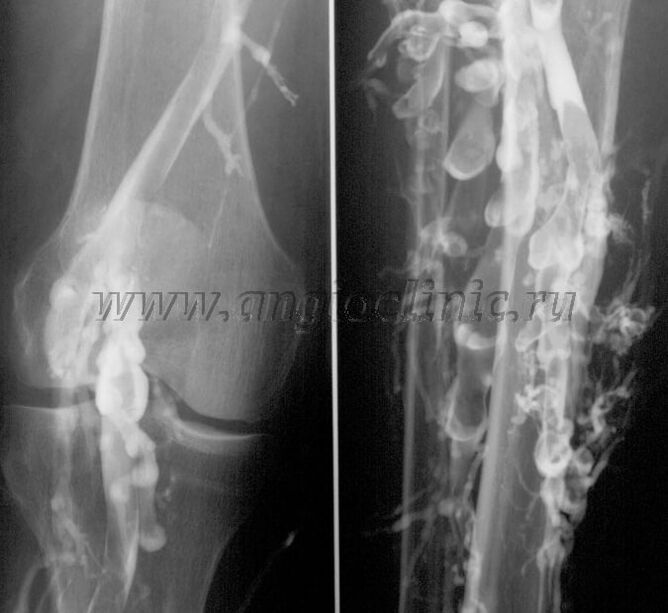

Venografi kontras

Biasanya, pemindaian ultrasonografi cukup untuk diagnosis lengkap patologi vena, namun dalam beberapa kasus perlu mempelajari hubungan antara keadaan sistem vena dalam dan superfisial, terutama jika terjadi kekambuhan varises dan varises sekunder.

Untuk mengatasi masalah tersebut digunakan pemeriksaan rontgen kontras. Vena safena ditusuk dan diberikan kontras. Pergerakan kontras diamati pada monitor mesin sinar-X, dan semua pengujian dan proyeksi yang diperlukan dilakukan. Saat ini, venografi untuk varises sangat jarang digunakan.